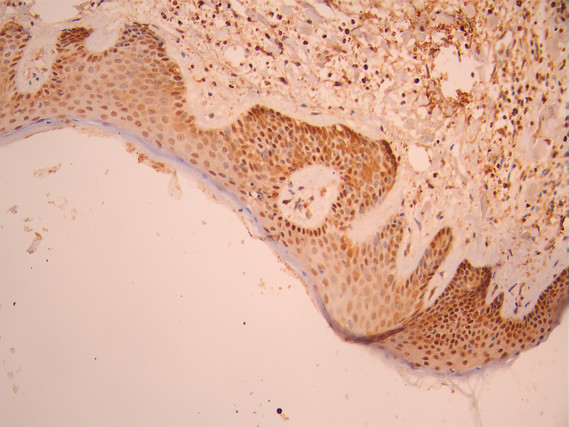

IHC image of CSB-RA261359A0HU diluted at 1:100 and staining in paraffin-embedded human skin tissue performed on a Leica BondTM system. After dewaxing and hydration, antigen retrieval was mediated by high pressure in a citrate buffer (pH 6.0). Section was blocked with 10% normal goat serum 30min at RT. Then primary antibody (1% BSA) was incubated at 4°C overnight. The primary is detected by a Goat anti-rabbit polymer IgG labeled by HRP and visualized using 0.05% DAB.

Application Recommended Dilution IHC 1:50-1:200 -